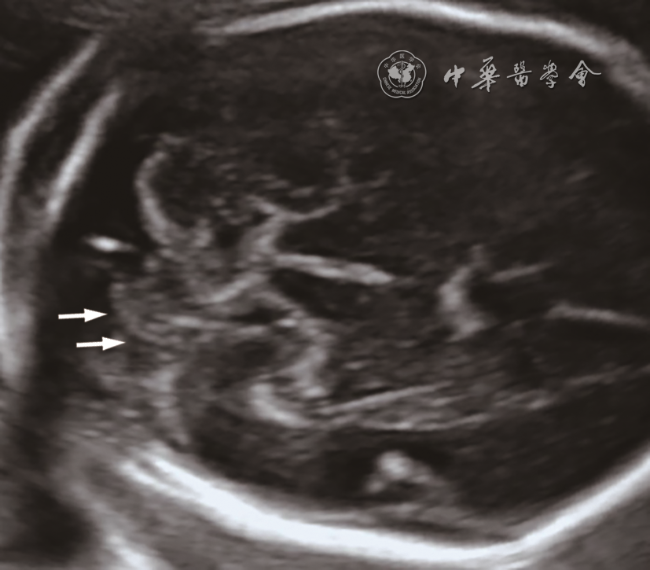

1. 产前超声检查:与正常胎儿小脑图像比较(图1),6例胎儿小脑横切面声像图示小脑形态均失常,左右不对称,一侧小脑减小,形态失常,伴或不伴蚓部异常,对侧小脑半球大小、形态正常(图23);其中4例小脑蚓部发育不全或发育不良,1例合并蛛网膜囊肿,1例合并神经元移行障碍和胼胝体发育不全。产前超声诊断:左侧小脑发育不全4例,右侧小脑发育不全2例。

图1 中孕期正常胎儿小脑超声表现:左右小脑半球对称,边界规则

图2 孕22周胎儿(例6)产前颅脑二维超声声像图。小脑横切面声像图示小脑形态失常,右侧小脑半球明显变小;小脑蚓部正常

图3 孕25周胎儿(例5)产前小脑二维超声声像图及产后脑部解剖图。图a小脑横切面声像图示左侧小脑半球明显变小,蚓部显示不清;图b能量多普勒显示左侧小脑半球小而血供较差(箭头所示);图c产后超声声像图示残存的左侧小脑半球实质(箭头所示);图d产后解剖图(颅底观)示左侧小脑下部几乎缺如